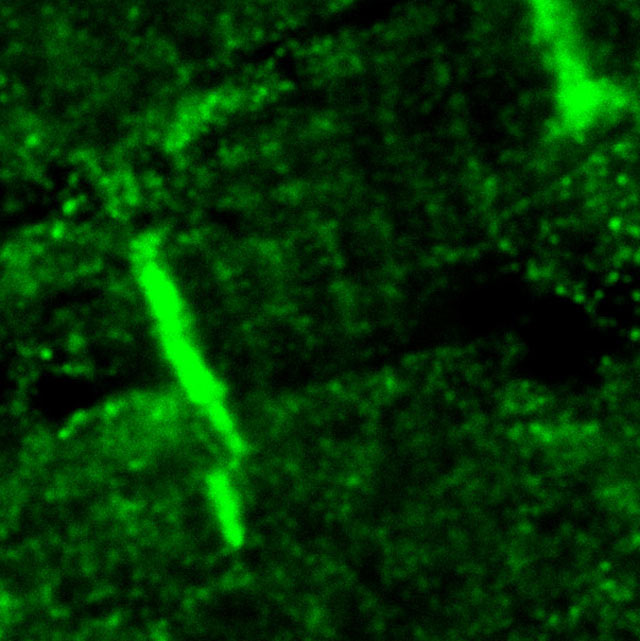

Dr Ian Holt & Professor Glenn Morris currently study the role of nuclear membrane proteins (emerin, SUN, nesprins) and intercalated disc proteins (POPDCs, XIRPs) in cardiac conduction, especially in relation to human genetic disease (Emery-Dreifuss and other muscular dystrophies with cardiac conduction defects) and with particular interest in the short isoforms of nesprins that are found only in skeletal and cardiac muscles.